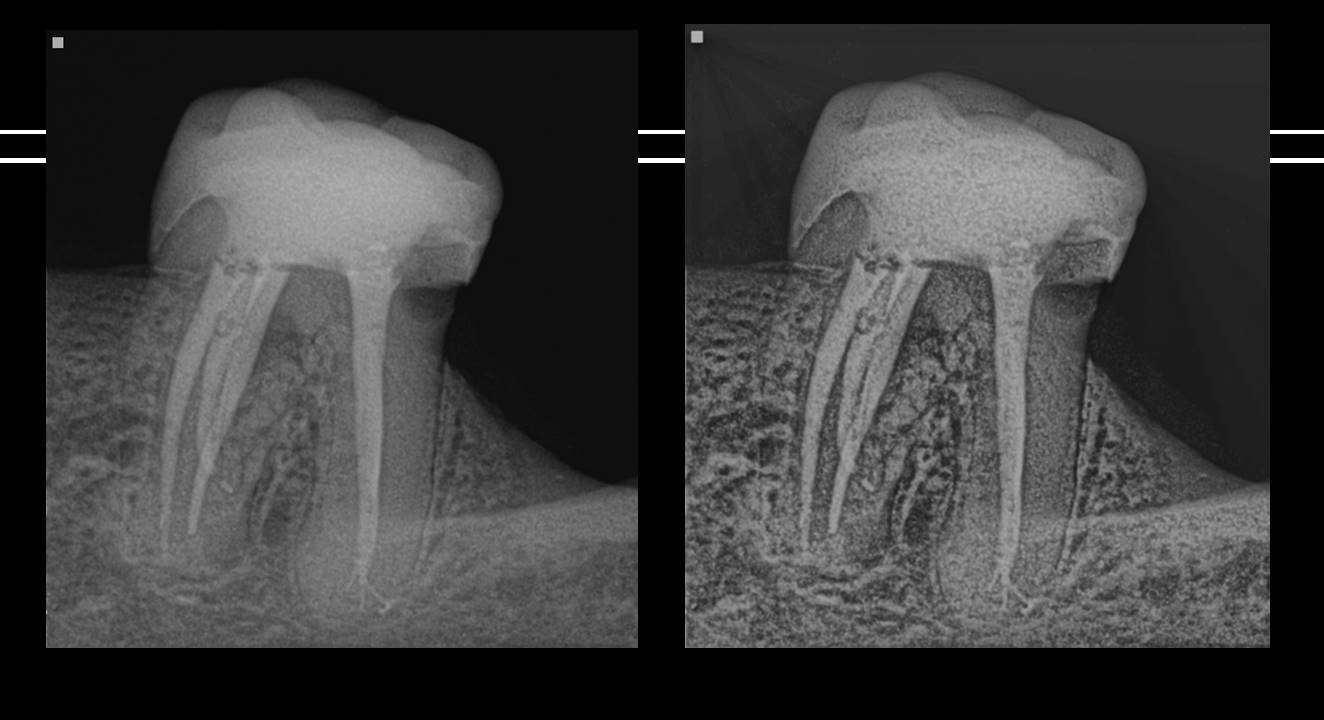

Acompanhamento molar inferior com 3 canais mesiais